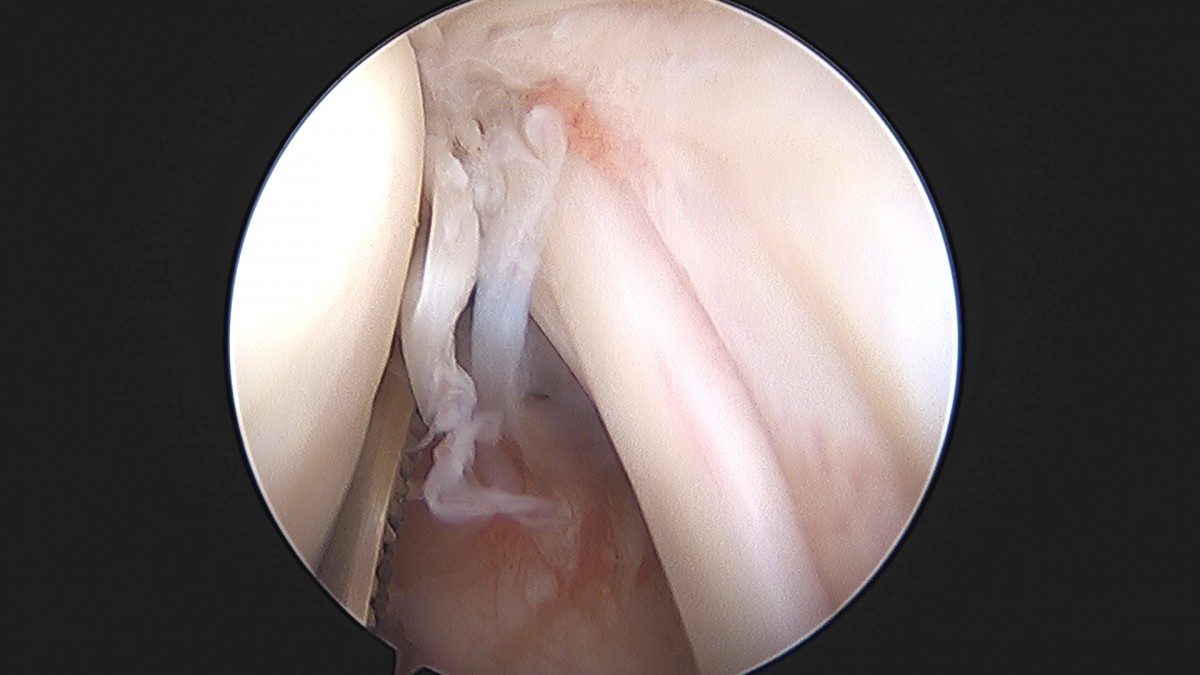

이재상원장님 어깨 견봉하 감압술 및 관절낭 이완술 주혜O 환자

dae765e4d9ac96aee867c9d6292d8784_1758003912_7954.jpg